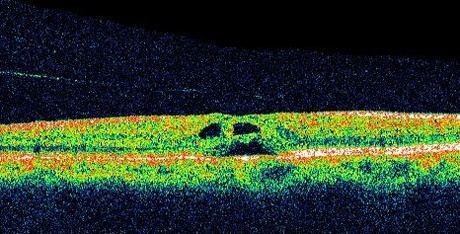

黄斑円孔とは、網膜の中心部の黄斑に穴(孔)があいてしまう病気です。穴自体はとても小さなものですが、最も視力に関係がある部分にできるため、視力に大きな影響があらわれます。

弁のようになっていた網膜が外れて分離すると、円孔が完成しステージ3となります。

この状態になると視野の真ん中だけが見えなくなり、視力は0.1ぐらいに低下します。